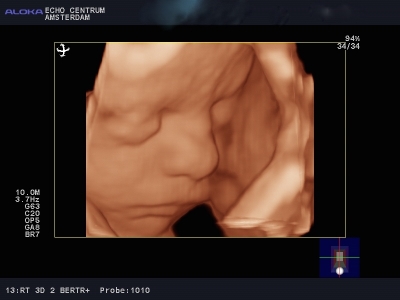

Onlangs had ik een hele leuke ervaring. Ik ben een gepensioneerd gynaecoloog, en was vroeger zeer begaan met mijn verloskundige patiënten. Mijn schoondochter en zoon nodigden mij uit om mee te gaan naar een "pretecho"van dr. Papa in Amsterdam. Wij, gynaecologen, hebben geweldige vooroordelen tegen een zogenaamde pret echo en vinden ze vaak overbodig. Nou dit pakte anders uit. We werden verwelkomd door een bijzonder charmante, leuke en vlot bespraakte Nederlandse Antiliaan: Elvin Papa, arts echoscopist. Daar zat hij in zijn spreekkamer, in een prachtig pand, achter een prachtig echo apparaat, dat voor mijn toenmalige ziekenhuis te duur was om voor ons gynaecologen aan te schaffen!! Alles werd getoond, het hele lichaampje van de baby. Alle organen, het geslacht, hart en bloedvaten noem maar op. Prettig was dat je in 3D een hele goede indruk krijgt van het gezichtje. Het hele onderzoek verliep voorspoedig en was heel relaxed. Papa doet veel aan nascholing en houdt de ontwikkelingen op echo gebied heel goed bij. Echo onderzoek kan heel vervelende zaken aan het licht brengen. Wij hadden een goed nieuws echo, dus dat is feest en lol. Belangrijk lijkt mij wel dat je met een slechte echo bij Elvin Papa in goede handen bent. Hij zal weten hoe je te troosten en hoe je door te verwijzen. Hopelijk hoeft dat niet vaak. Ik wens hem nog veel succes toe.

Vandaag was ik samen met mijn vrouw, moeder en neefje bij Dr. Papa. De naam alleen al maakt je vrolijk, dan zie ik mijn kleine mannetje weer op het scherm (oeps heb ik verraden wat het word). Dr. Papa legt alles zo haarfijn uit en het aller mooiste en belangrijkste is dat het kindje alles heeft en alles doet. In 3d zie ik zijn gezichtje en geloof het of niet, ik zie mijn kleine even lachen, mama zegt hij lijkt op jou, de glimlach die ik toen kreeg is er de hele dag gebleven, en nu ik dit schrijf verschijnt hij weer.

Wauw! Wat een bijzonder moment, het zien van ons eerste kindje in 3D! De neus van de een en de kleine krulletjes van de ander die al te zien waren. Te gek!